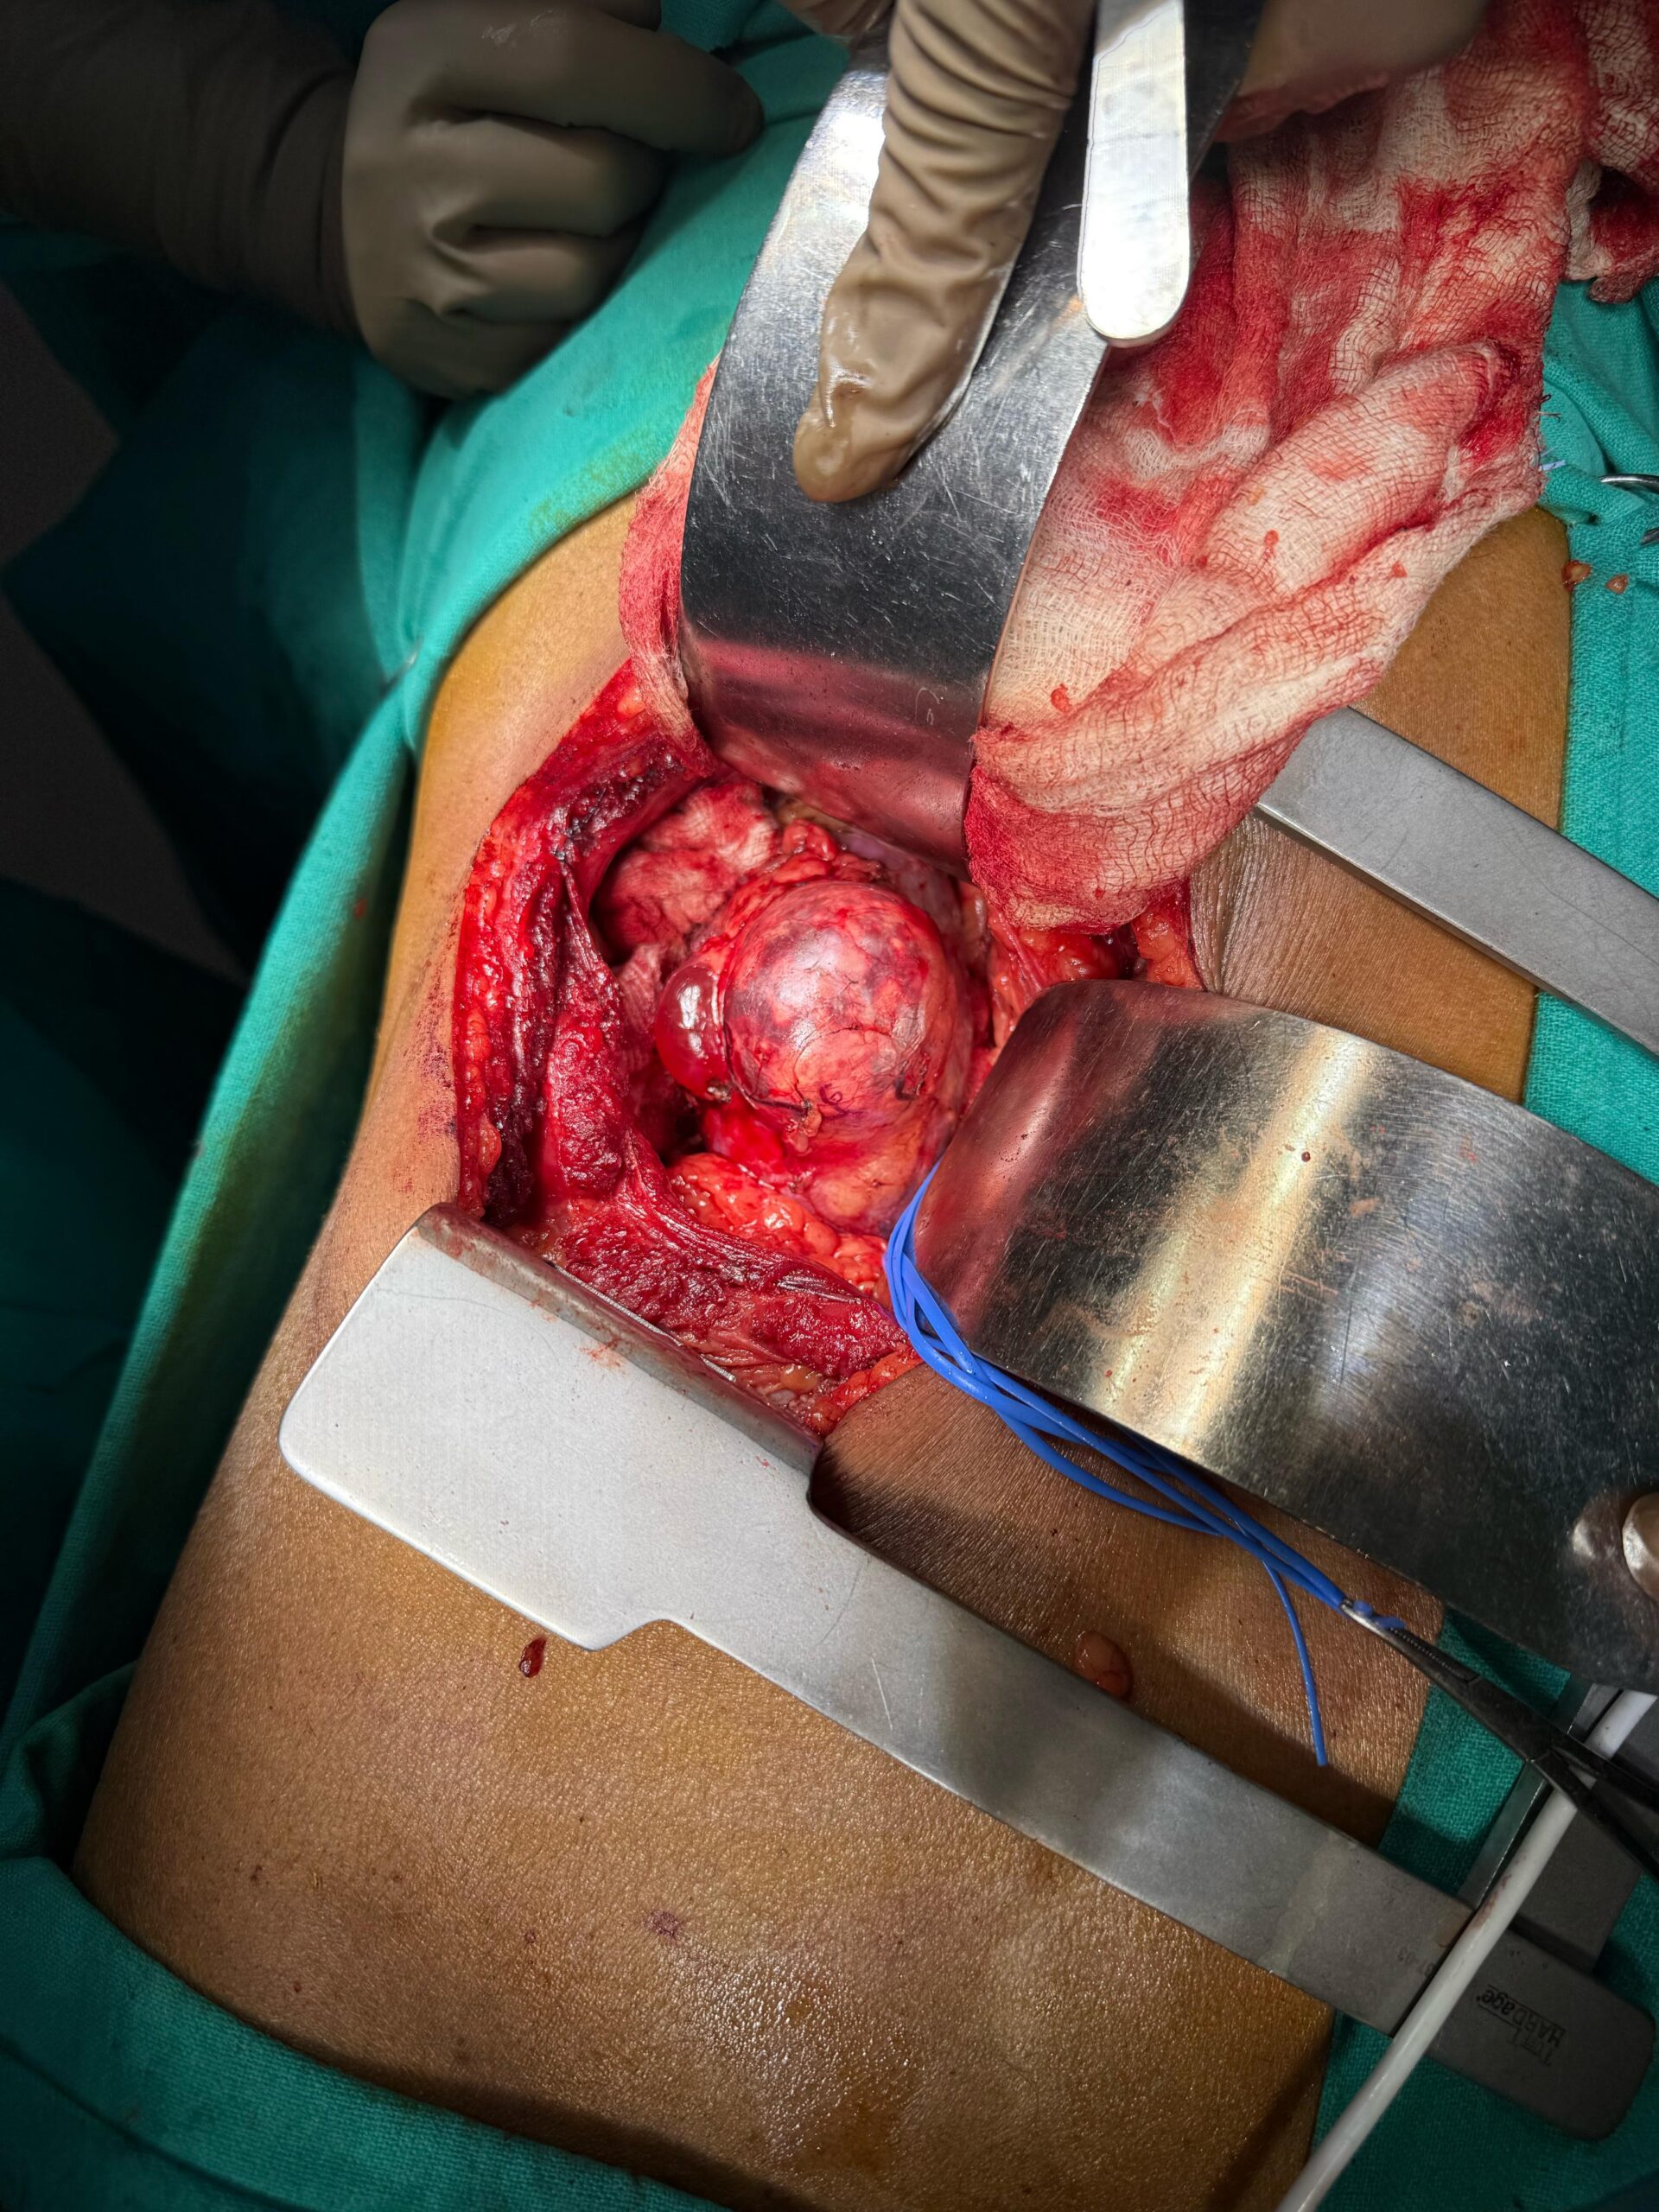

Our Gallery